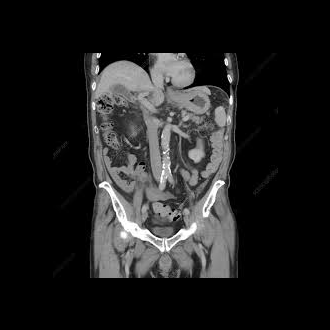

A CT scan is an x-ray procedure that is enhanced by a computer and gives out a three-dimensional view (referred to as a “slice”) of a particular part of the body.

While dense tissue can block some areas during standard x-ray image procedures, CT scans create a three-dimensional view by using a computer to combine different slices, showing all bone and tissue.